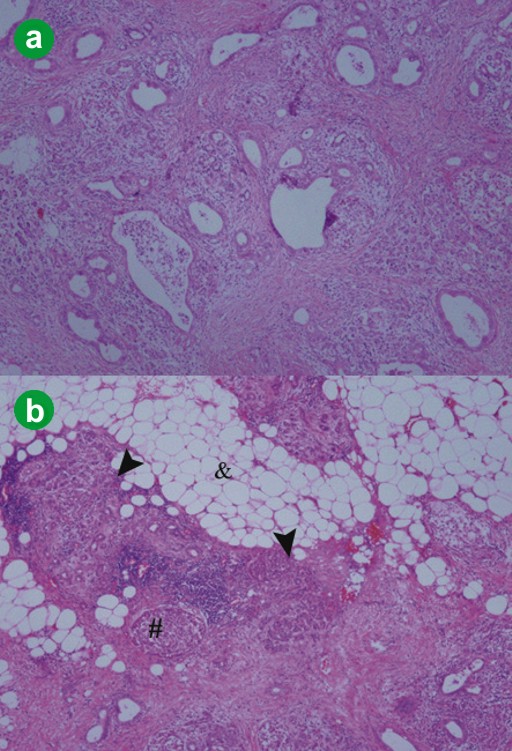

Figure 2. The cut surface demonstrated diffuse fatty infiltration (#) and contained a well-demarcated white to grayish tumor (&). |

Figure 3. a. Histological features of the tumor revealed abundant fibrosis and duct lesions with various atypia (x100). b. In the periphery of the tumor, normal duct-like lesions, islets of Langerhans (#) and acinar atrophy (arrow heads) were observed and, around the tumor, abundant normal adipose tissue (&) was seen (x100). |

The characteristic histological features of this minute pancreatic ductal adenocarcinoma were as follows. First, the pancreatic ductal adenocarcinoma was composed of abundant fibrosis, called the desmoplastic reaction, and various duct lesions. However, such duct lesions as could be distinctly diagnosed as adenocarcinoma were present sparsely in the vicinity of the center of the tumor. The desmoplastic reaction is one of the characteristic features of an invasive pancreatic ductal adenocarcinoma [3, 8], and it has been hypothesized that cancer cells within the desmoplastic reaction area grow as the result of a mechanism, such as tumor-stroma interaction [9]. Hence, the evident presence of the desmoplastic reaction, in spite of a minute pancreatic ductal adenocarcinoma and the sparse presence of cancer cells within the desmoplastic reaction area, appeared to be valid for the very early features of a pancreatic ductal adenocarcinoma. Second, normal duct-like lesions, mucinous metaplasia and acinar atrophy were observed only in the periphery of the tumor. It is thought that these components may have originally been present in the scattered acini in which this pancreatic ductal adenocarcinoma occurred and they were later included in the tumor with progression of the pancreatic ductal adenocarcinoma. In addition, the features of no vessel and lymphatic permeation and no neural invasion support the fact that this case was likely to be the early stage of an invasive pancreatic ductal adenocarcinoma.

Lipomatous pseudohypertrophy was first described in 1931 [12] but it is a rare disease and the specific etiology of lipomatous pseudohypertrophy remains unknown. At CT imaging, this patient demonstrated typical features [13]. Histologically, the pancreatic acini showed marked atrophy and loss, but the islets of Langerhans were relatively preserved; hence, it was thought that glucose tolerance was preserved. In the residual scattered acini, low-grade PanINs, mucinous metaplasia, acinar atrophy, dilated ducts and slight lymphocytic infiltration were shown with a considerably high frequency. Altinel et al. reported that scattered acini do not show signs of injury, such as cellular attenuation, inspissated secretions or tubular complex formation [14]. However, it is unknown whether the above features of the acini in this patient occurred in association with diffuse fatty infiltrations or a minute pancreatic ductal adenocarcinoma because there have only been a handful of case reports about lipomatous pseudohypertrophy. In the literature, there are only three reports of pancreatic carcinomas associated with lipomatous pseudohypertrophy: one squamous cell carcinoma and two adenocarcinomas [14]. To date, 30 cases of lipomatous pseudohypertrophy have been reported [14], but the study of carcinogenesis in lipomatous pseudohypertrophy patients has been extremely limited. In this patient, two risk factors, advanced age and smoking, might be involved in the possible occurrence of pancreatic cancer. Until now, it has been unclear whether lipomatous pseudohypertrophy should be considered as a risk factor for pancreatic ductal adenocarcinoma. However, if lipomatous pseudohypertrophy of the pancreas is observed, careful attention should be paid to the risk of carcinogenesis.